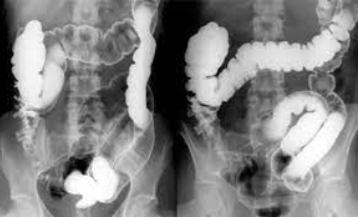

Figura 2: Série de posições no enema opaco. Fonte: Radiopaedia

Figura 3: Série de posições no enema opaco. Fonte: Radiopaedia

Figura 4: Série de posições no enema opaco. Fonte: Radiopaedia

Figura 5: Série de posições no enema opaco. Fonte: Radiopaedia